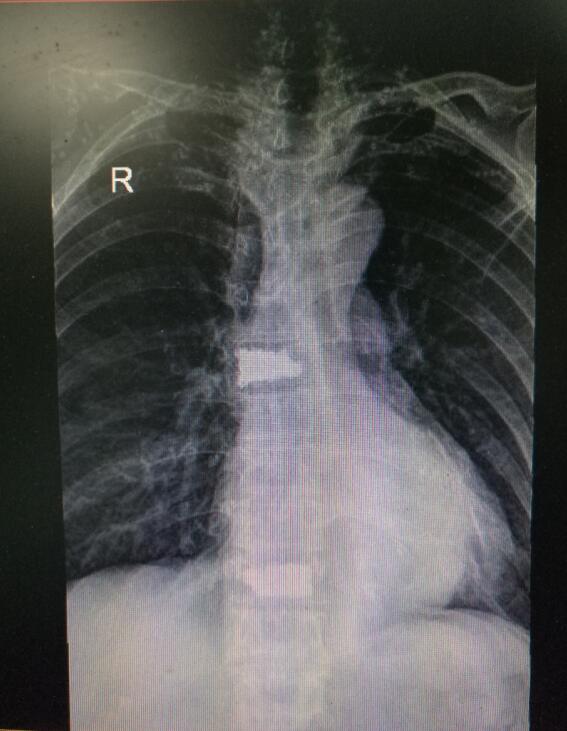

術(shù)后DR(數(shù)字化的x射線)